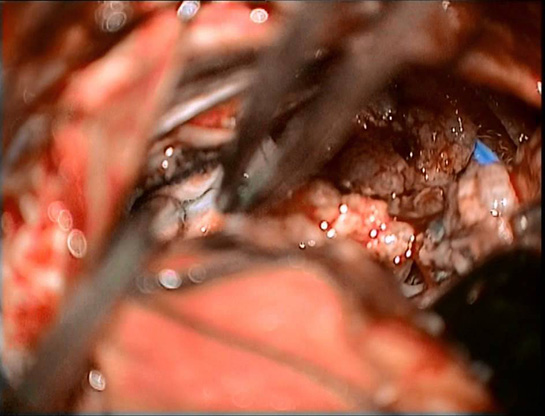

Beyin tümörü ameliyatı, beyin içerisindeki tümörlerin cerrahi olarak çıkarılması amacıyla gerçekleştirilen bir tıbbi müdahaledir. Bu tür bir operasyon, birçok risk ve komplikasyon barındırmakta olup, hastaların ameliyat sonrası süreçlerinde dikkat etmeleri gereken önemli noktalar bulunmaktadır. Bu yazıda, beyin tümörü ameliyatının riskleri, ameliyat sonrası bakım ve iyileşme süreçleri hakkında detaylı bilgiler sunulacaktır. Beyin Tümörü Ameliyatı Nedir?Beyin tümörü ameliyatı, beyin dokusundaki anormal hücrelerin çıkarılması için yapılan bir cerrahidir. Tümörler, iyi huylu (benign) veya kötü huylu (malign) olabilir. Cerrahinin amacı, tümörün tamamen çıkarılması, hastanın yaşam kalitesinin artırılması ve beyin fonksiyonlarının korunmasıdır. Ameliyat RiskleriBeyin tümörü ameliyatı, diğer cerrahi işlemler gibi çeşitli riskler taşımaktadır. Bu riskler arasında: